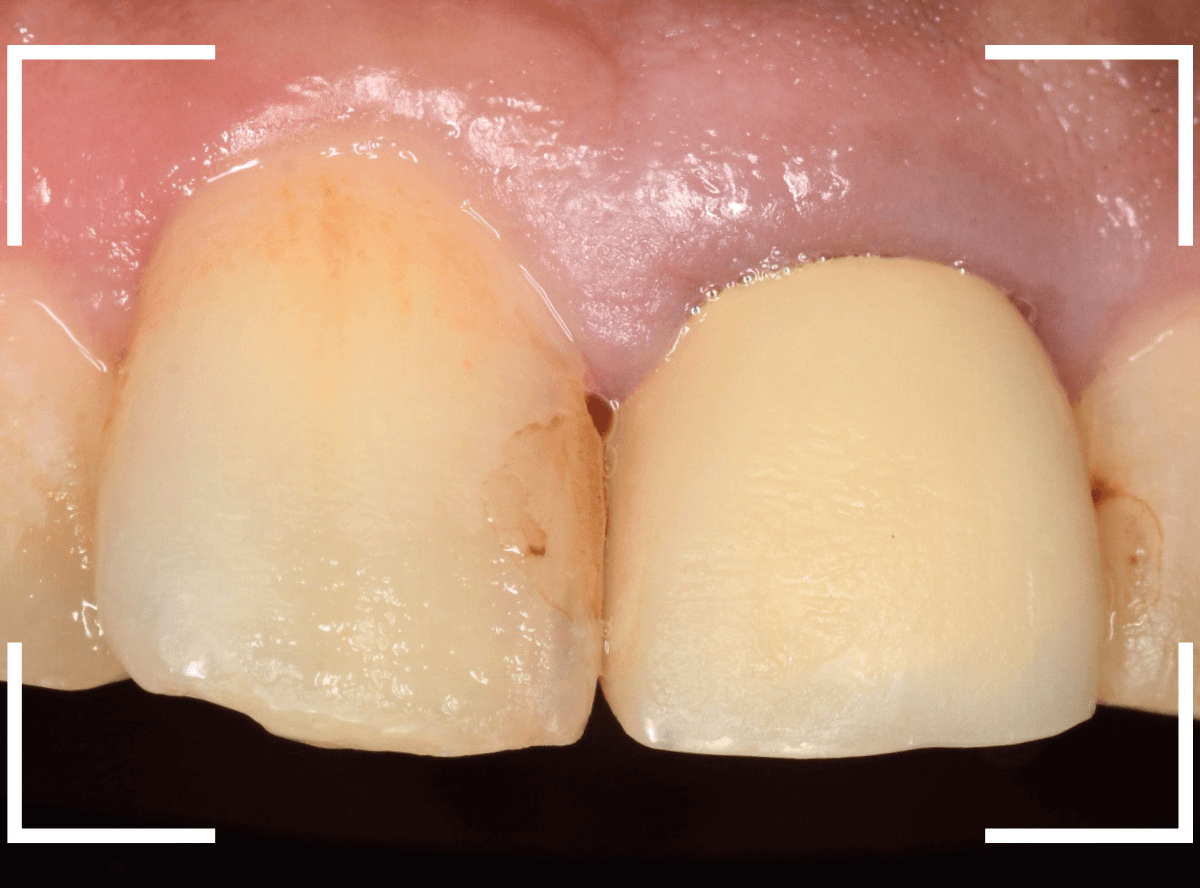

以前に治療した上のさし歯を綺麗にやり直したいというご相談の患者さんです。

保険診療で行うさし歯「レジン前装冠」が入っています。

「レジン前装冠」は裏から撮影した写真を見ていただければわかるように、銀歯の上にレジン(プラスチック)を盛ったさし歯で、実質的には銀歯です。

銀歯の上にプラスチックを盛るために、歯をかなり大きく削る必要があったり、短期間で劣化・変色する(この方の差し歯も劣化してのっぺりした黄土色になっています)、金属の色素が歯肉に溶け出して歯肉が黒くなる(メタル・タトゥー)などのデメリットがあります。